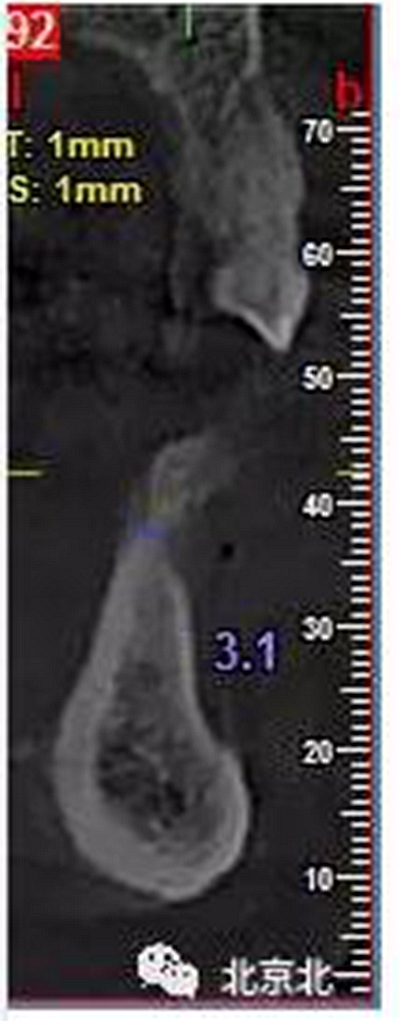

患者術(shù)前片, 最窄骨寬度僅僅3mm,34-35牙位缺失,

CBCT顯示如下圖

如何種植?